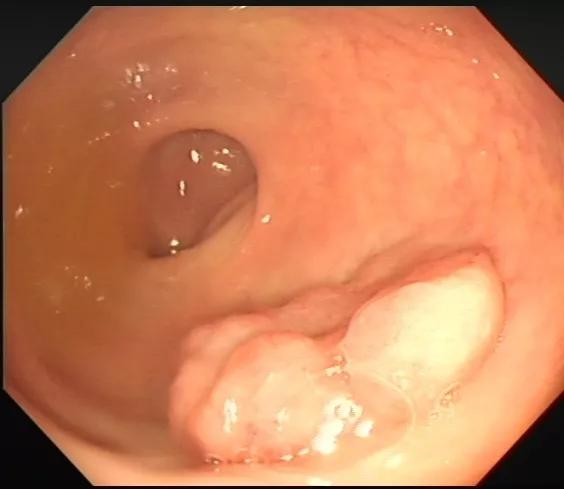

再比如我们做肠镜发现了肠腔肿瘤,也无法判断肿瘤侵润与多深?到了哪一层?

而超声内镜扫描观察就能简单判别:下图